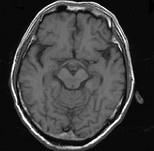

问题 男,头痛7月余,伴左侧面部麻木,疼痛剧烈时伴恶心,无呕吐,请根据所提供图像,选择最可能的诊断()

选项 A.垂体瘤 B.颅咽管瘤 C.生殖细胞瘤 D.脑膜瘤 E.胶质瘤

答案 B